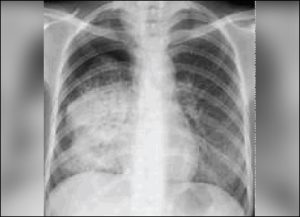

વર્ષ 2025 સુધીમાં ભારતને ટ્યુબરક્યુલોસિસ (ટીબી) મુક્ત કરવાના દાવા અને વાસ્તવિક્તા વચ્ચે હજુ ઘણો તફાવત છે. ગુજરાતમાં આ વર્ષના પ્રથમ 45 દિવસમાં જ ટીબીના 15748 કેસ નોંધાઇ ચૂક્યા છે. આમ, દરરોજ ટીબીના સરેરાશ 350 નવા કેસ નોંધાય છે.

છેલ્લા 5 વર્ષમાં 5.86 લાખ કેસ નોંધાયા જેમાં અમદાવાદ જિલ્લામાં સૌથી વઘુ 87063 કેસ છેલ્લા 5 વર્ષમાં જ ગુજરાતમાં 5.86 લાખ લોકો ટીબીની ઝપેટમાં આવી ચૂક્યા છે. પાંચ વર્ષના આ સમયગાળામાં સૌથી વઘુ કેસમાં સુરત જિલ્લો 64288 સાથે બીજા સ્થાને છે.